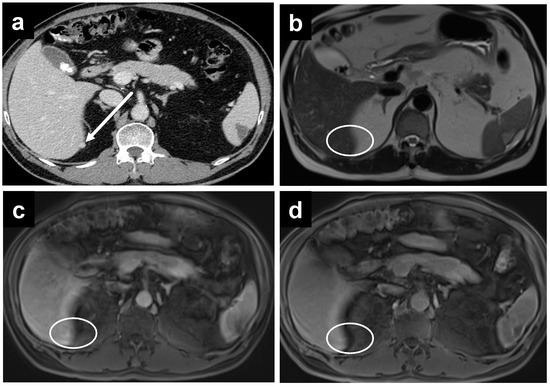

3.3. Evaluation of PCI